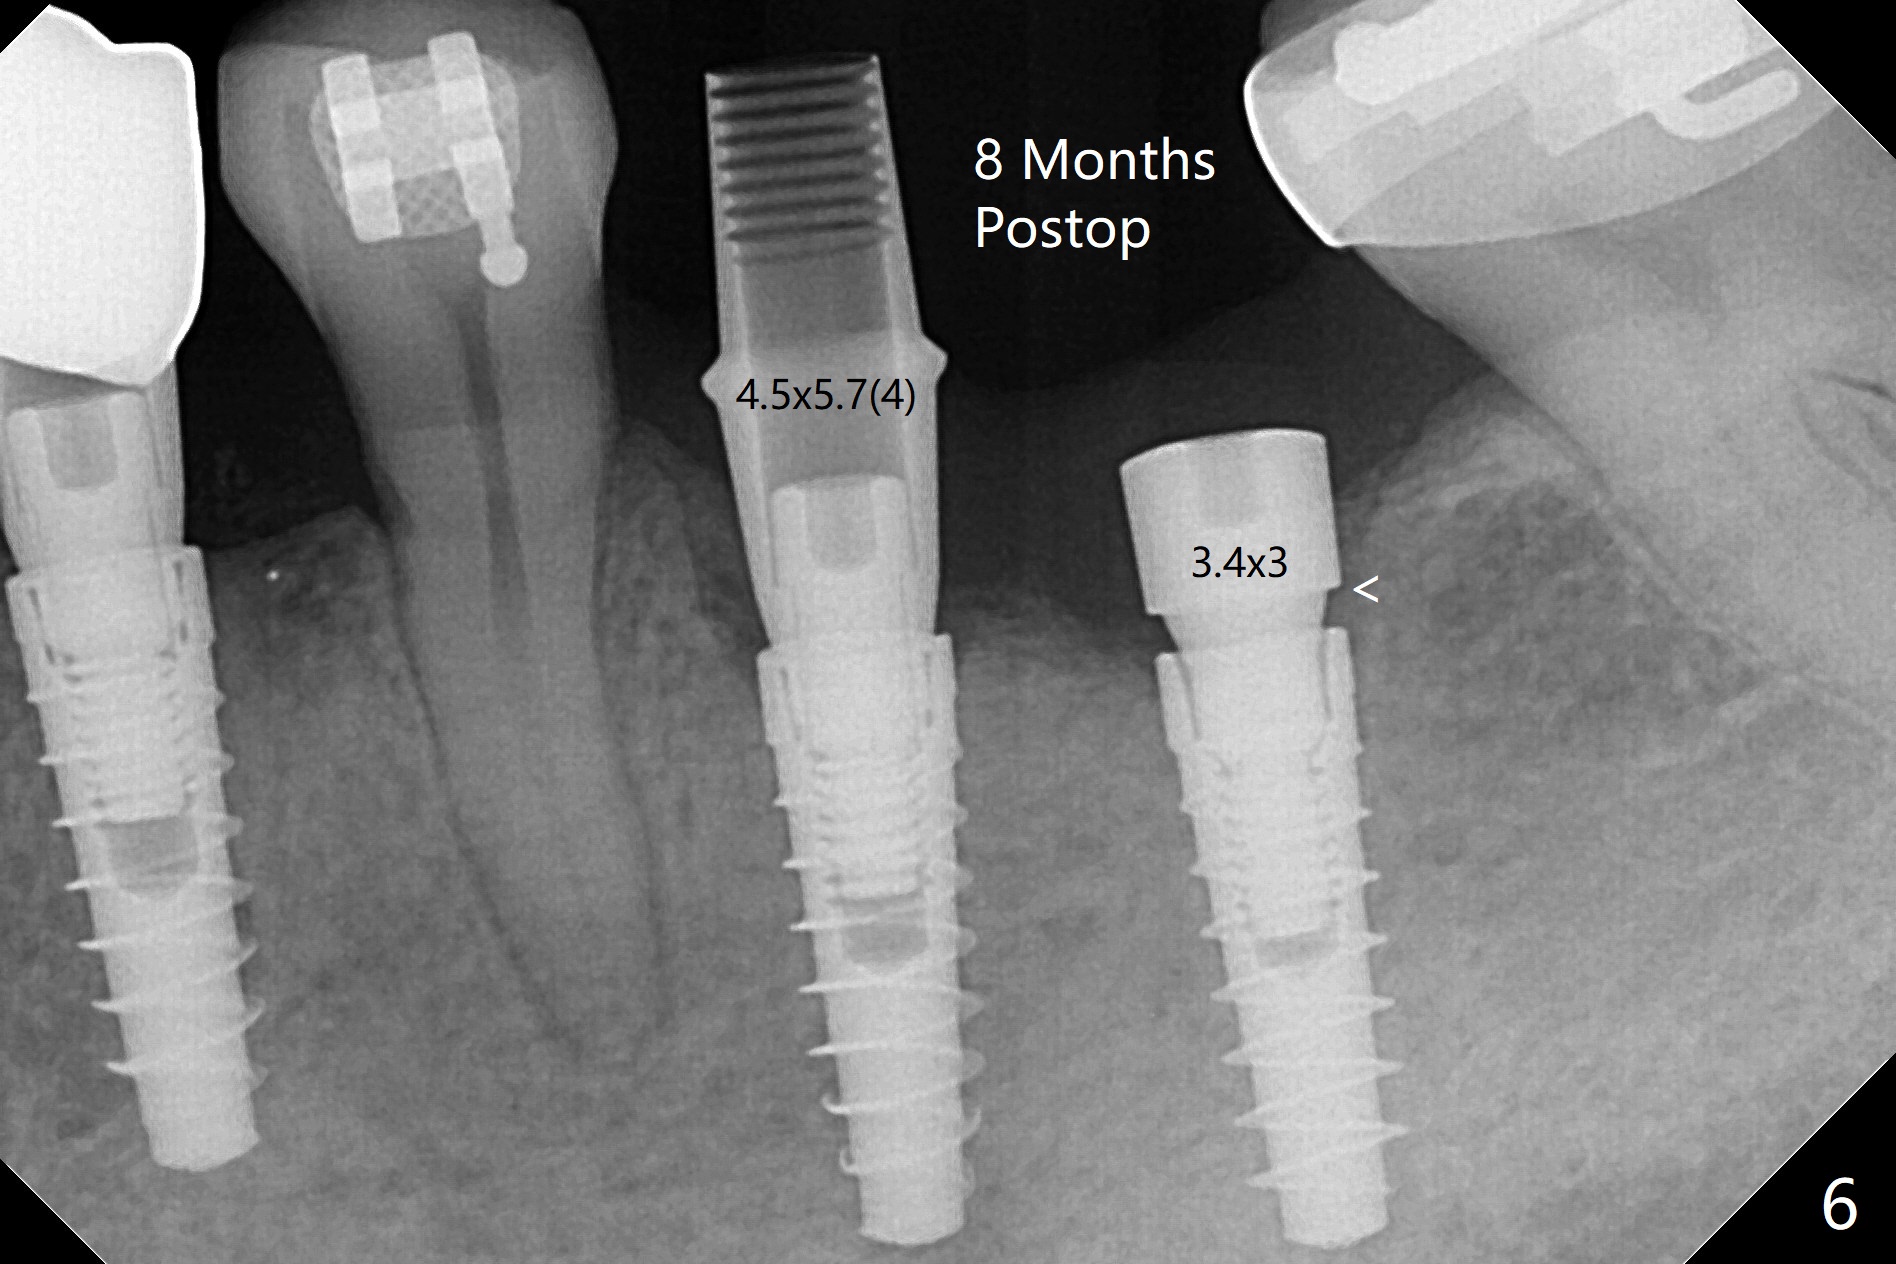

左下6,7导板设计种植两个小植体,牙槽嵴角化龈狭窄(图一:*),切开,钻洞,6处骨质密度高,钻头与植体直径必须一样,但是为了保证稳定性,最后1.5毫米钻头小0.5毫米,植体最后1-2毫米必须倒旋一次才能控制扭力不超过40Ncm,术后即刻根尖片显示4,6根尖部(密度2200单位,图二)螺纹弯曲(<),而7(密度670单位)钻头比植体小0.5毫米,植入扭力也大约40Ncm,不过螺纹没有变形。祸不单行,6植体冠部舌侧螺纹暴露约1毫米,放入自体骨后,盖膜(6个月),4-0铬羊肠线减张缝合(图三),牙槽嵴好像增宽了。术后两周伤口愈合(图四)。术后4.5个月切开暴露,尽管需要外科钻头去除植体冠部骨质,6舌侧植体螺纹仍暴露,放置4.5x3毫米愈合基台,7放置4x4(3)毫米修复基台(图五),但是接近8牙冠,无法修复,必须做局部牙齿矫正。术后7个月7放置3.4x3毫米愈合帽,6放置4.5x5.7(4)毫米修复基台,手拧紧,做临时牙冠,垫高,开始矫正;一个月后基台松动,扳手拧紧(30Ncm);7处3.4x3毫米愈合帽没有就位,由于远中牙槽嵴阻挡(图六:<)。